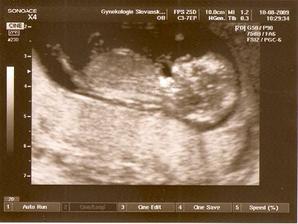

berija

13. bře 2009

Nelinka -tak jde čas🙂